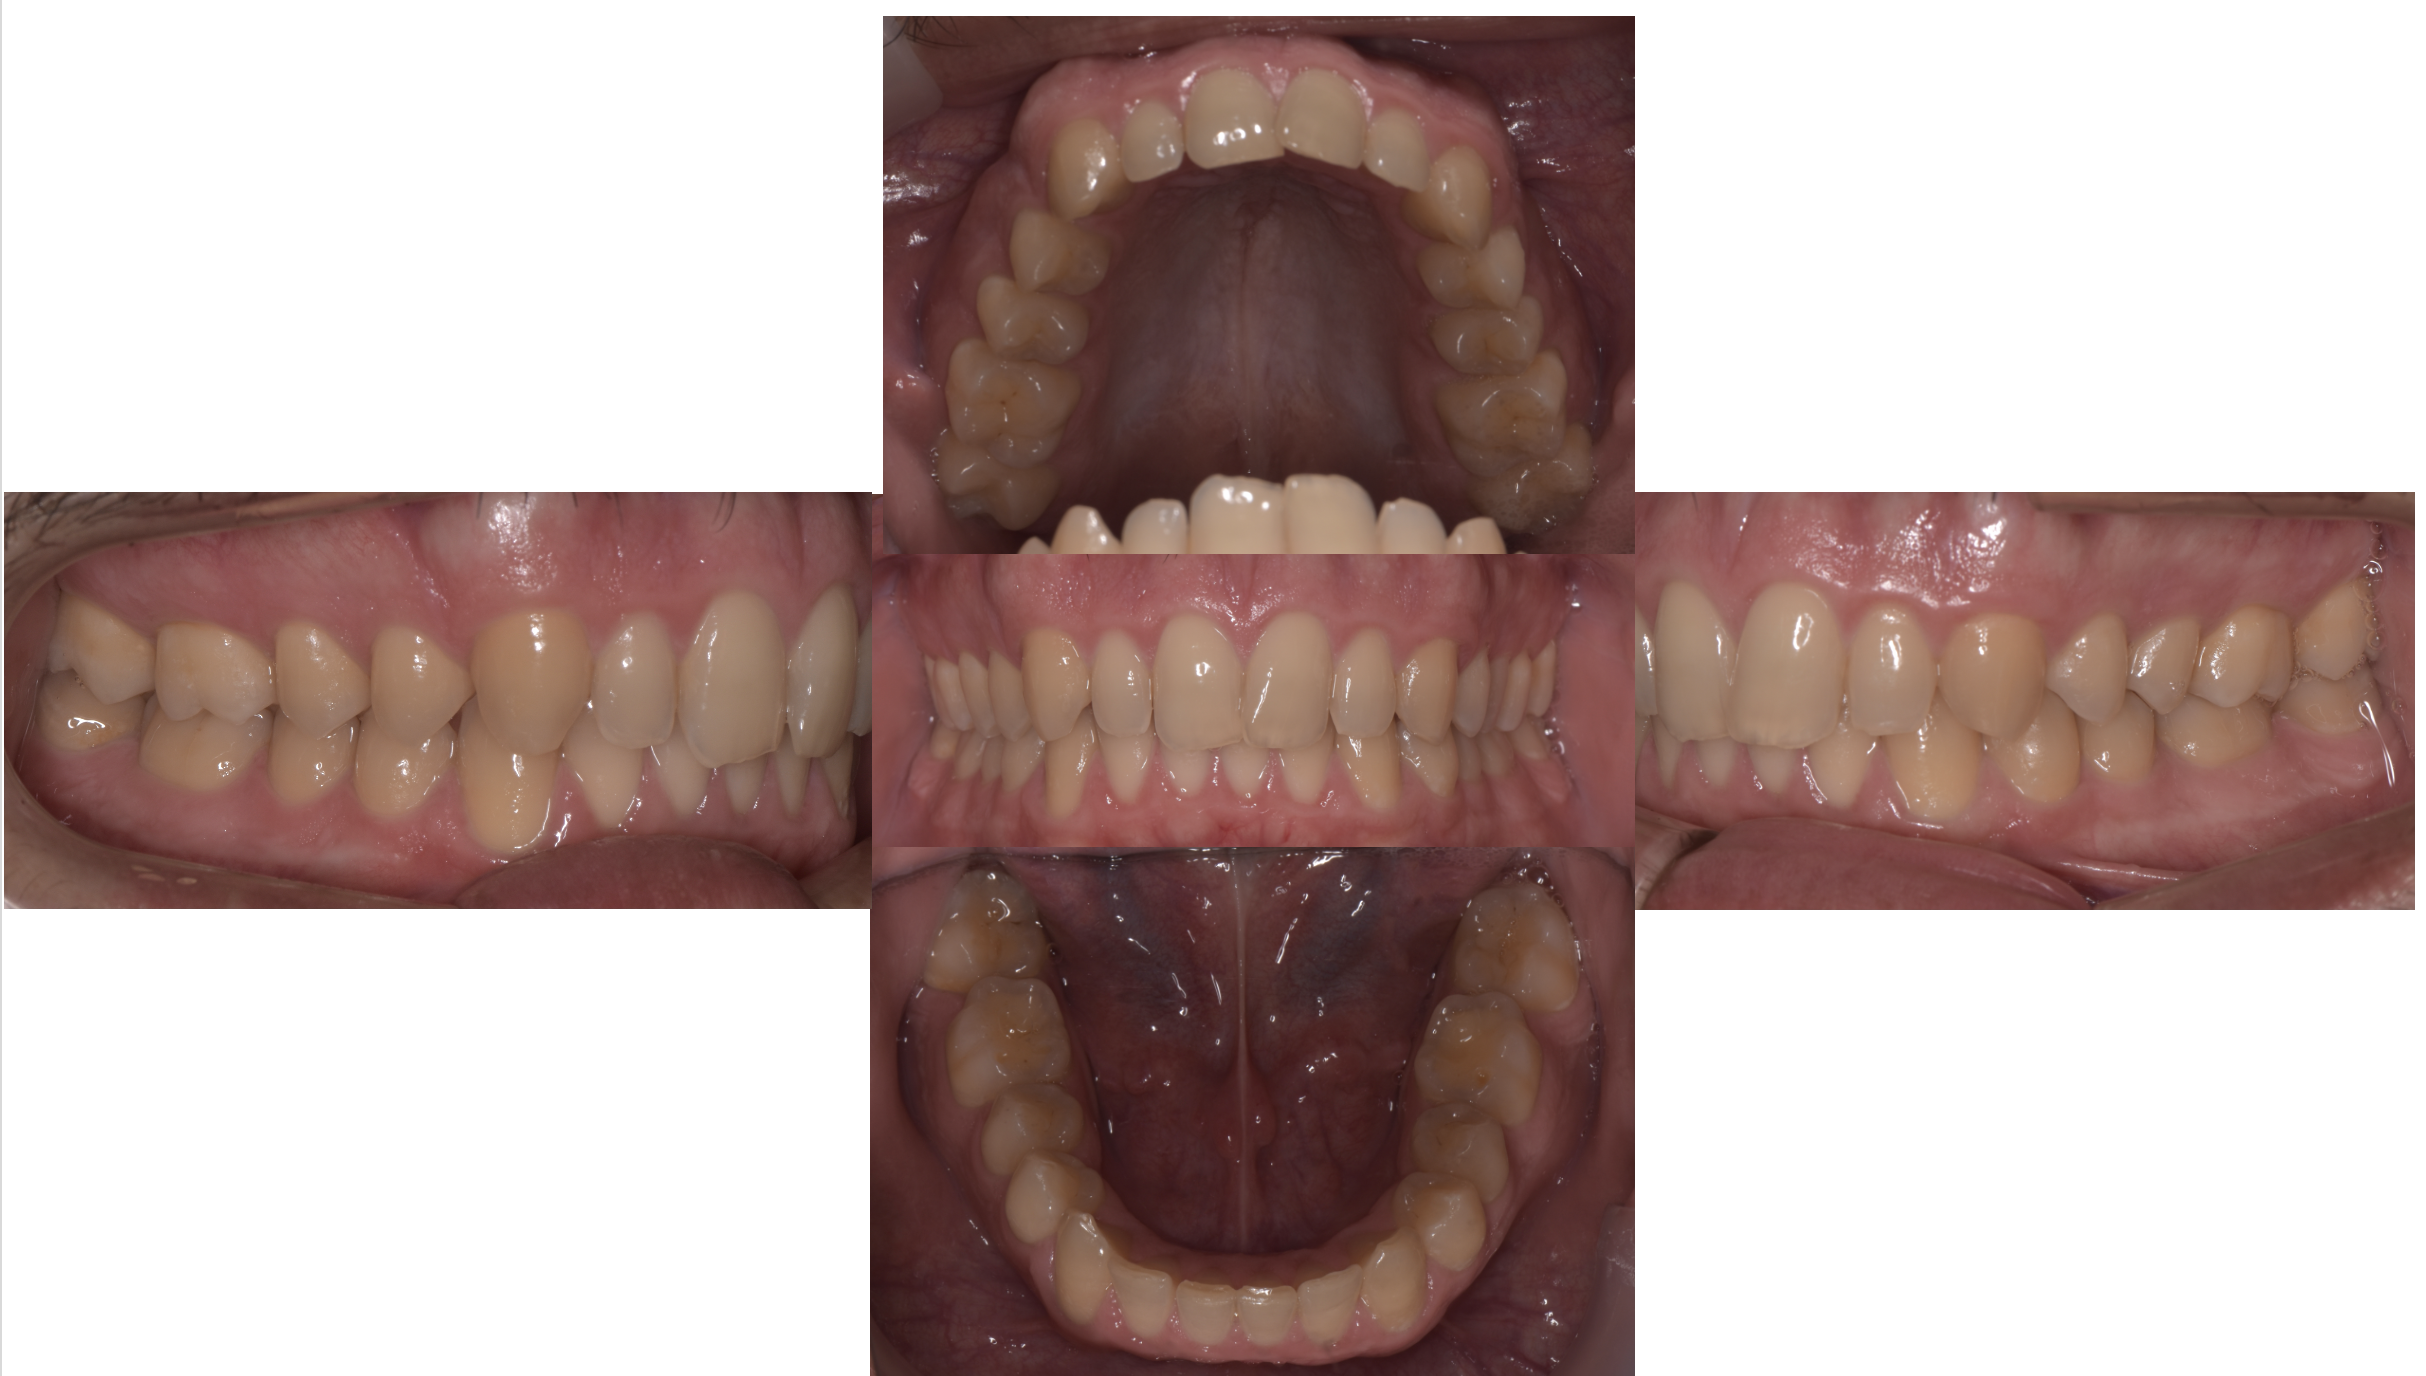

初診時には、デンタルドックという精密検査を行い、MRI撮影(左右)、レントゲン、口腔内写真などを確認しましたが、歯科的な問題は咬み合わせ以外には見られませんでした。

術前のT-scanで、咬み合わせとしては奥歯に力が偏っているのが確認できます。しかし、患者さんご本人にはその違和感や症状を自覚されていませんでした。

T-scan による検査を行ったことで、咬み合わせに問題があることがわかりましたが、その他の検査では異常は見られませんでした。

この段階で「問題のない歯を削るかどうか」という点を患者様と相談し、「メニエール病が少しでも改善するのであれば、歯を削っても構わない」とご同意をいただいた上で、治療に進むこととなりました。